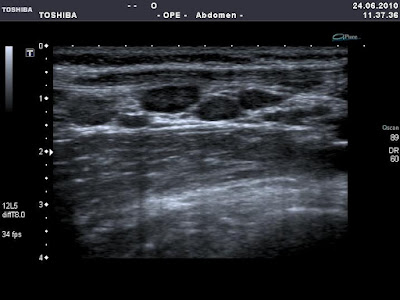

7 eves kislany diffuz hasi fajdalommal, minimalis nyomaserzekenyseggel a jobb alhasi regioban. A labor negativ.